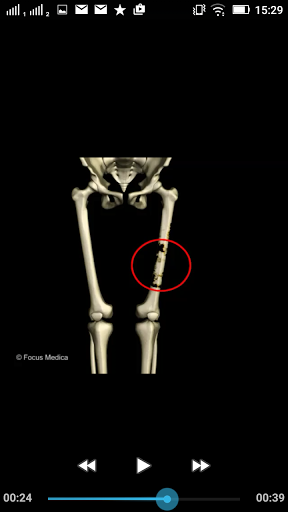

The FOCUS Animated Pocket Dictionary of RHEUMATOLOGY is the first ever animated dictionary in the subject. A valuable reference for physicians and students alike, it covers 100 rheumatology related terms and definitions. All the definitions have been graphically described with the help of 3D animations and are accompanied by text definitions.

The Focus Animated Pocket Dictionaries are the world’s first ever animated dictionaries that provide definitions of medical terms with the aid of realistic and narrated 3D animations, complimented with text definitions. Terms arranged alphabetically making definitions easy to search. These unique visual dictionaries are excellent reference sources for health professionals, students and health consumers. The videos play independent of the internet once downloaded.